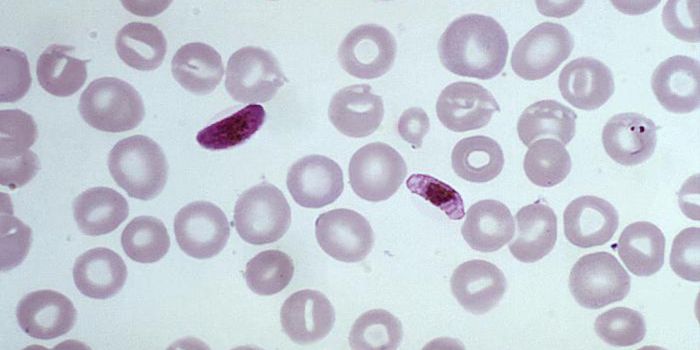

OCT 12, 2020Genetics & GenomicsMosquitoes can transmit the malaria-causing Plasmodium parasite to humans. Malaria was estimated to have caused the deat ...

SEP 01, 2020ImmunologyMalaria is one of the biggest ongoing threats to global health — over 200 million were infected and almost half a ...